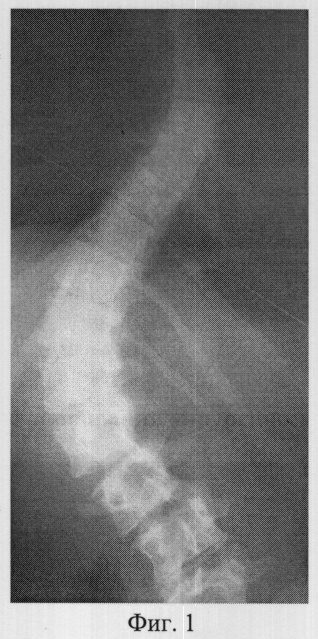

Фиг.1 – рентгенограмма в прямой проекции сколиотически измененного позвоночника больной К. до операции (грудопоясничная локализация);

В СарНИИТО ей были выполнена рентгенография в стандартных проекциях: фасная (фиг.1) и боковая (фиг.2) рентгенограммы.

По фасной рентгенограмме определены показатели позвоночника:

– угол сколиотической деформации по Кобб: стоя – 73°, лежа – 64°;

– индекс стабильности по Казьмину – 0.86;

– определена протяженность дуги в 13 позвонков (от Th5 до L5),

– вершина деформации Тh12.